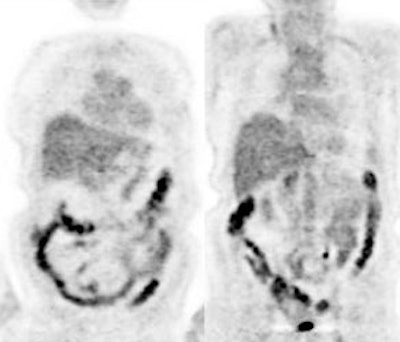

Large bowel activity is common and can be focal, segmental, or diffuse [40]. Focal intense uptake in the colon is an uncommon finding (1-2% of cases) and should be further evaluated with colonoscopy to exclude a neoplastic process which can be found in a large percentage of patients (61 to 86% of focal abnormalities are found to be premalignant or malignant) [40,93,96,114,123,2227]. The visualization rate of colorectal polyps increases with polyp size and the severity of histologic dysplasia [197]. Acute diverticulitis is an inflammatory condition that can result in focal colonic uptake [96]. Segmental colonic uptake is usually related to inflammation, while diffuse uptake is usually not associated with underlying bowel abnormality [40]. Areas of active Crohn's disease will also demonstrate FDG accumulation [170]. Uptake in the cecum and right colon is usually higher than in other colonic segments [4,40]. This may be related to abundant lymphoid tissue in this region [54]. FDG accumulation can also often occur in segments or large sections of the colon after colonoscopy- possibly due to a non-specific inflamation [20]. A perirectal area of artifactually increased curvilinear tracer uptake has been described and has been felt to be related to movement of gas within the rectum [230]. An air pocket present in the rectum during the PET acquisition where there was no gas during the CT exam results in overcorrection for attenuation at the margin of the rectum [230]. Adjacent extremely high tracer concentration in the urinary bladder is felt to contribute to the artifact [230].

|

Normal bowel activity: Faint

heterogeneous bowel uptake is common. |

Intense right colon activity: Note the intense activity in the right colon in this asymptomatic patient. Increased activity in the right colon can sometimes be seen. Note uptake in the patients left upper lobe lung cancer. Focal activity in the left upper abdomen was related to the stomach. |

Diffuse large bowel activity: Diffuse increased colonic FDG uptake was seen in this asymptomatic patient. Diffuse uptake is usually not associated with underlying bowel abnormality. |

Focal colonic uptake associated with colon cancer: This patient had focal tracer uptake in the region of the cecum. CT demonstrated a soft tissue mass which was found to be a primary colon cancer on colonoscopy. Focal areas of colonic tracer uptake should be further evaluated. |